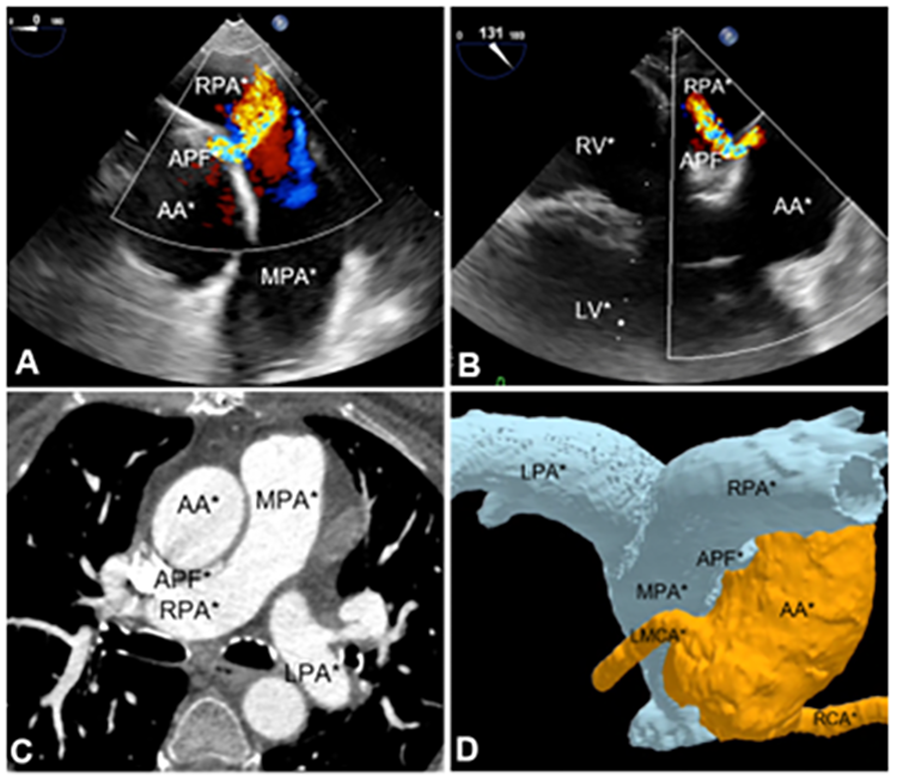

Further investigation with transesophageal echocardiography (TEE) confirmed the presence of the fistula, which measured 2 mm at the aortic orifice (Figures 1A,B and Supplementary Videos S1, S2), located approximately 30 mm above the aortic valve plane. In the midesophageal long-axis view of the ascending aorta, the maximum pressure gradient across the fistula was 78 mmHg. This resulted in high pulmonary output, with an estimated pulmonary artery systolic pressure of 44 mmHg.

Figure 1

Imaging methods utilized for aortopulmonary fistula diagnosis. (A) TEE midesophagus ascending aorta short-axis section. (B) Midesophageal long-axis section. (C) Angiotomography of aortic and pulmonary vessels. (D) 3D angiotomography reconstruction. APF, aortopulmonary fistula; AA, ascending aorta; MPA, main pulmonary artery; LPA, left pulmonary artery; RPA, right pulmonary artery; LMCA, left main coronary artery; RCA, right coronary artery; RV, right ventricle; LV, left ventricle.

Subsequently, computed tomography angiography (CTA) with 3D reconstruction of the aortic and pulmonary vessels was performed to determine the optimal correction strategy and assess the distance between the fistula and the coronary arteries (Figures 1C,D and Supplementary Videos S3). CTA revealed an aortopulmonary fistula located 26 mm above the aortic root and 38 mm below the brachiocephalic artery. The fistulous tract measured 10 mm in length, with an aortic orifice measuring 3 × 2 mm and a pulmonary orifice measuring 6 × 2 mm.